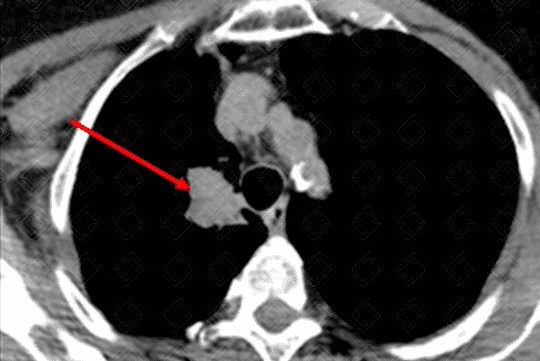

Descrição da f igura 6: Tomografia computadorizada de tórax evidenciando massa, com densidade de partes moles (seta vermelha), na periferia do lobo inferior esquerdo, suspeita para neoplasia pulmonar.